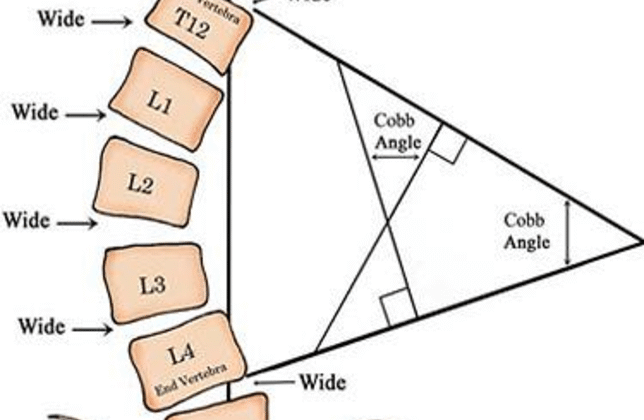

كيف يتم قياس زاوية كوب؟

تصوير الأشعة: يُجرى للمريض وهو واقف أو مستلقٍ.

تحديد الفقرات النهائية: اختيار الفقرة الأكثر ميلًا في أعلى وأسفل الانحناء.

رسم الخطوط: رسم خطين على الفقرات المائلة ثم قياس الزاوية الناتجة.

يتميز هذا القياس بالدقة، لكنه قد يتأثر ببعض العوامل مثل: وضعية المريض، اختلاف تقييم الأطباء، ودوران الفقرات.

هل هناك حدود أو عيوب لزاوية كوب؟

رغم أنها الأداة الذهبية للتشخيص، إلا أن لها بعض القيود:

تعطي صورة ثنائية الأبعاد فقط ولا توضح التشوهات ثلاثية الأبعاد.

نسبة خطأ بسيطة (3–5 درجات).